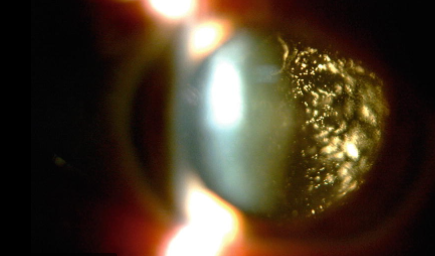

Asteroid hyalosis appears as hundreds of tiny sparkling lights inside the eye.

Because of the calcium buildup in your eye caused by AH, your doctor will notice a white or sparkling lights inside your eye. AH will be confirmed with dilatation of your pupils and inspection of your eyes with a device called a slit lamp.